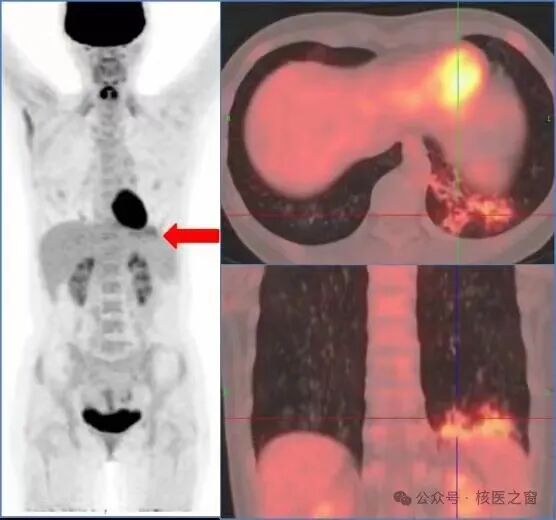

2、明确肿瘤侵犯程度,协助医生为您选择合适的治疗方案

图片